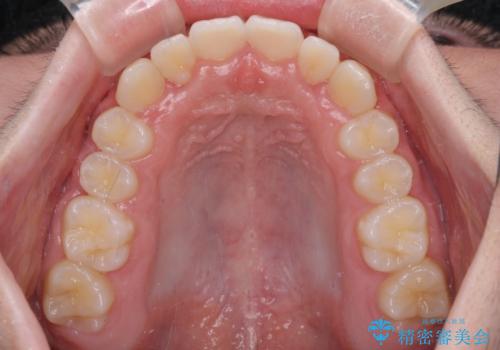

中学生のワイヤー矯正 クロスバイトを短期間で改善

- 前歯のクロスバイトを気にして来院された患者様です。

中学生であることから、治療期間を短縮できると判断し、ワイヤー矯正にて短期間で治療を行うこととしました。

叢生のため磨き残しの多い歯列でしたが、1年弱で治療を終了でき、磨き残しや歯肉の腫れが著しく改善されました。